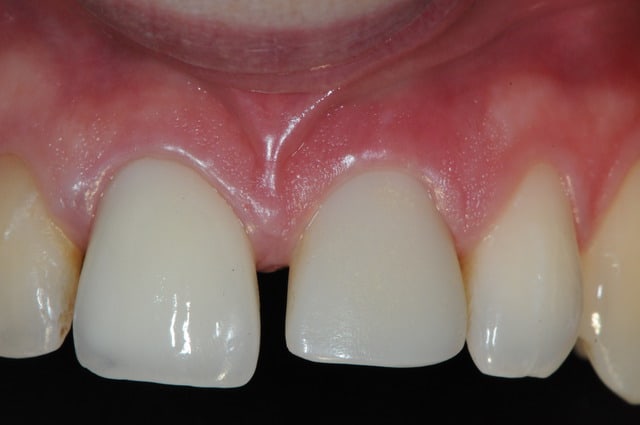

voici des news du deuxième cas clinique.

nous sommes à j+7

je pense que la gencive devrait encore remonter dans les 3 prochains mois...

les couronne ont été posées hier justement!

comme promis...

il faudra attendre un peu pour voir ce que ça donnera pour la gencive dans quelques mois. dommage que le patient ne voulait pas de conjonctif enfouie pour épaissir sa gencive.